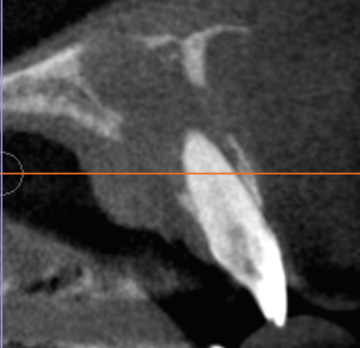

診断の鍵はCT(CBCT)|「2つの病変」を見極めて治療戦略を分ける

前歯部の病変は平面レントゲンだけでは重なりが生じやすく、

「根尖性病変なのか」「嚢胞が主体なのか」「併発なのか」が分かりにくいことがあります。

当院ではCT(CBCT)を用い、

- 根尖部の感染(根尖性歯周炎)

- 切歯管周囲の嚢胞性病変(切歯管嚢胞)の関係を立体的に評価し、原因に合わせて治療を組み立てます。

術後経過|3ヶ月で骨ができてきている所見を確認

術後3ヶ月の時点で、画像上、骨形成(骨ができてきている)ことを確認しています。

骨の治癒・成熟は数ヶ月〜年単位で進むため、今後も定期的に経過を追いながら